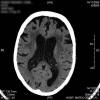

AVC amplio de territorio de A. cerebral media